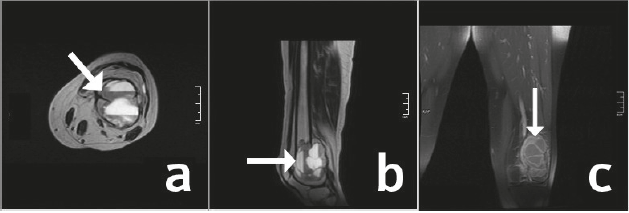

Paciente femenina de 23 años de edad con antecedente de Linfoma de Hodking clásico con esclerosis nodular tratado hace 7 años con 6 ciclos de quimioterapia. Acude a consulta por cuadro clínico de dolor incapacitante de aproximadamente 2 meses de evolución. En las secuencias T2 FSE y T1 FSE de resonancia magnética se observa una lesión de aproximadamente 4.1 x 3.8 x 2.5 cm con una marcada alteración de la morfología del tercio distal del fémur izquierdo que modifica la trabeculación ósea normal, con abombamiento cortical posterior. Se identifican múltiples cavitaciones quísticas con un doble contenido correspondientes a niveles hemáticos, compatible con Quiste Óseo aneurismático (Figura 2 a, b, c). Se decide llevar a cirugía donde se realiza escisión del tumor más osteotomía con dispositivo de fijación en fémur izquierdo. Se envía muestra a servicio de patología donde confirman el diagnóstico de quiste óseo aneurismático secundario a linfoma de Hodking clásico con esclerosis nodular.

Figura 2. RM plano axial T2 frFSE, plano sagital T2 frFSE, plano coronal T1 FSE (a, b, c) Se observa lesión expansiva de fémur distal con abombamiento cortical posterior y múltiples cavitaciones con nivel hemático en su interior sin reacción perióstica ni cambios inflamatorios en tejidos blandos.